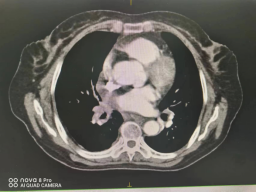

(四)肺癌

行IMRT治疗半程CT图像对比图